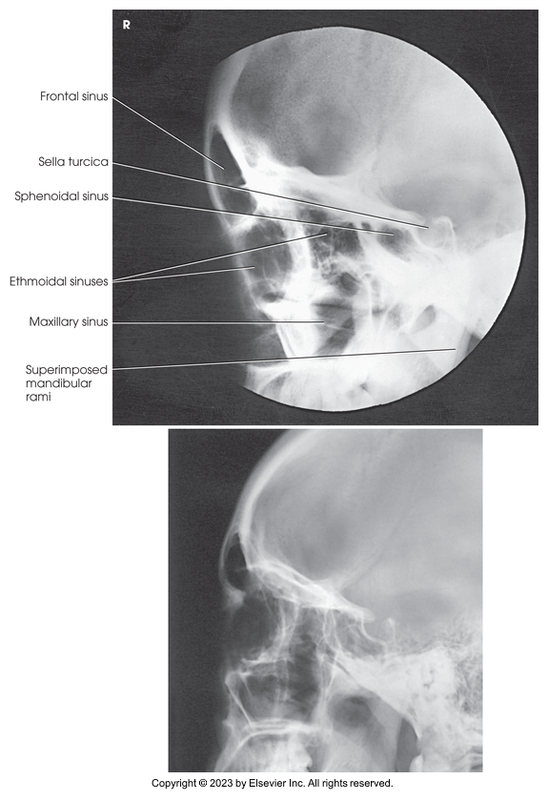

Lateral Projection of Paranasal Sinuses

Lateral projection of skull

Lateral of the sinuses